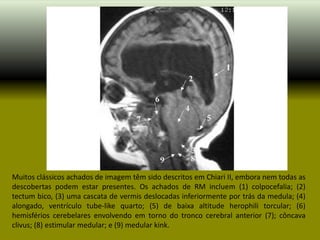

Muitos clássicos achados de imagem têm sido descritos em Chiari II, embora nem todas as

descobertas podem estar presentes. Os achados de RM incluem (1) colpocefalia; (2)

tectum bico, (3) uma cascata de vermis deslocadas inferiormente por trás da medula; (4)

alongado, ventrículo tube-like quarto; (5) de baixa altitude herophili torcular; (6)

hemisférios cerebelares envolvendo em torno do tronco cerebral anterior (7); côncava

clivus; (8) estimular medular; e (9) medular kink.